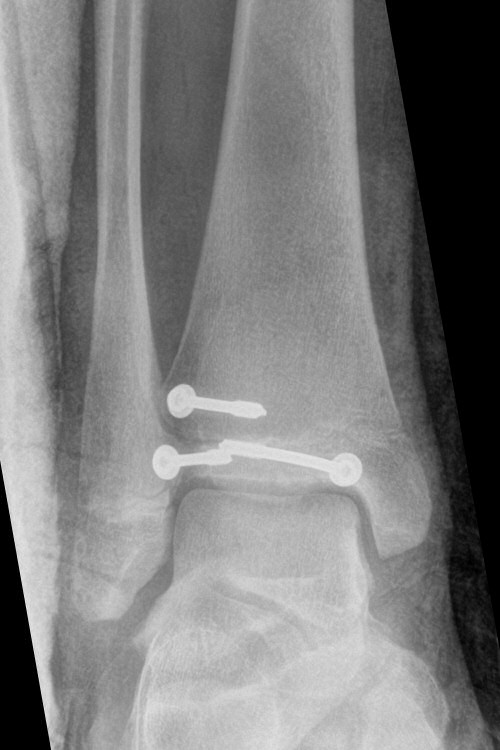

Exempel på triplansfraktur hos nästan färdigvuxet barn

Efter operation med skruvfixation

- Förbered för inläggning och snar operation, ofta med kanylerade skruvar. [2]